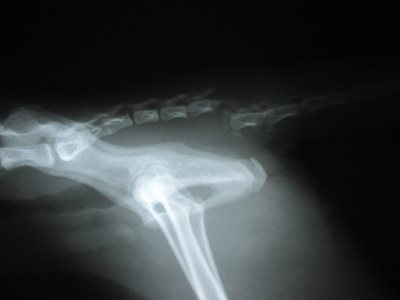

We x-rayed him and quickly found out what was going on. We confirmed that his tail was fractured and dislocated. However, what was more remarkable on the x-ray was the lack of intestines, stomach and liver. The abdomen looked quite empty! Where did they go? We then x-rayed the chest and found the missing organs. No wonder he was not feeling well.

How did this happen? We assumed that when Bill Murray went missing he sustained a significant injury like a fall from a great height OR being struck by a car. This caused his diaphragm (the muscle separating the chest and the abdomen) to have a tear or hole in it. The organs in the abdomen migrated up through this hole and crowded his chest cavity! It was amazing that he was still able to breathe, eat and walk around!